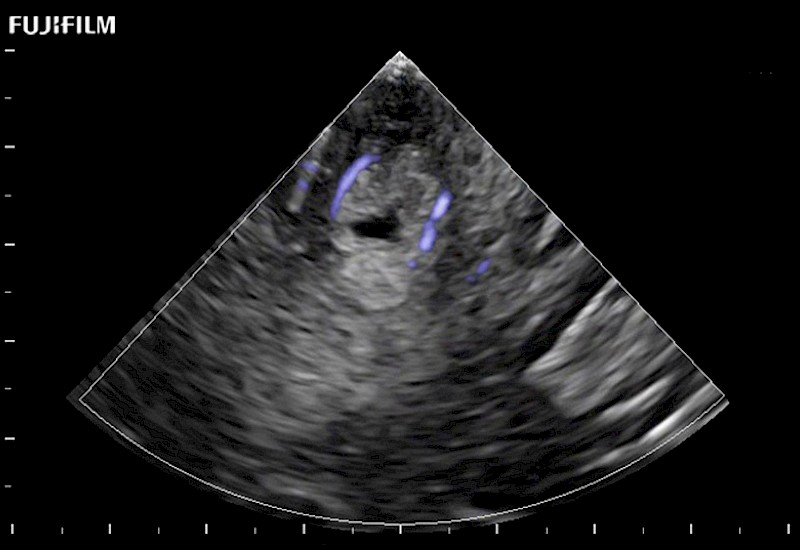

Exclusive 10mm side‐fire linear array transducer with 2.87mm diameter is ideal for real‐time visualization through and behind structures and instant, scalable definition of anatomy and vascularity including the ability to delineate and define tumor margins.

Main Specifications: